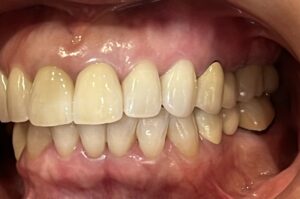

今回は、前歯のレイヤリングジルコニアセラミックの

治療をされた患者さまのご紹介です!

歯周治療、虫歯治療、審美治療の総合的な治療をおこないました。

修復の材料はほぼジルコニアセラミッククラウンで統一しています。

天然の歯は事前にホワイトニングを行い、全体的にトーンアップさせて、

それに合わせてカラーを決めています。

前歯のレイヤリングジルコニアはセラミストのデジタルトライインを行って

作製します!

全体的に綺麗になって患者さまもとても喜んでおられました♪